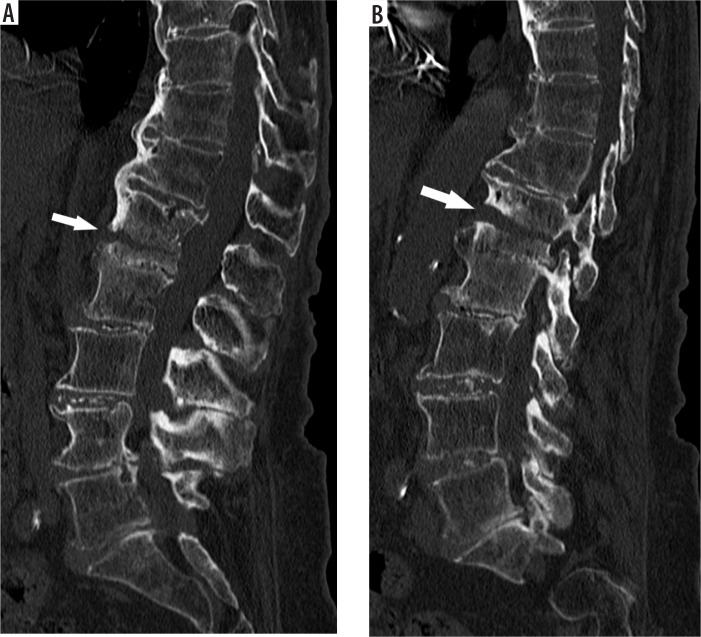

Results: A total of 65 patients with fractures through ankylosed segment or immediately adjacent segment (rigid spine group) and 307 controls were identified. Most rigid spine patients suffered minor trauma. In both groups most of the fractures were located in the thoracolumbar junction, and type A1 fractures were most common, followed by types A3 and A4. Multilevel fractures were more common in rigid spine patients (41.54% vs. 30.29%). Most of the rigid spine fractures (46.96%) were located within the fused spinal segment, with the midportion of the fused spinal segment being the most common location of types B and C fractures. Long-segment fusion was associated with unstable type B and C fractures. In short-segment fusion, single level type A fractures were most common. Spinal cord injury occurred only in patients with delayed diagnosis.

Conclusions: When plain films are used as a first-line diagnostic test for thoracolumbar spine trauma in stable patients without abnormal neurological signs or symptoms, and long-segment spinal ankylosis is observed, thoracolumbar CT should be used for further evaluation.